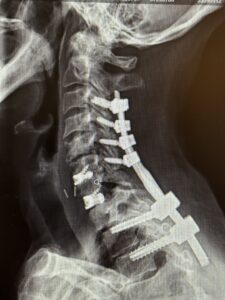

The patient underwent a one-day, two-stage procedure. Stage 1 was a C6-7, C7-T1 anterior cervical discectomy and fusion with reduction of the anterolisthesis and correction of the kyphosis.

Stage 1 was immediately followed by Stage 2 which was extension of her posterior instrumentation and fusion from C3 down to T3. Neuro-navigation was used to assist with the difficult anatomy of the upper thoracic spine.

The patient had an uneventful postoperative course with significant improvement in her preoperative symptoms and is now able to maintain a good posture (Fig 2 right).